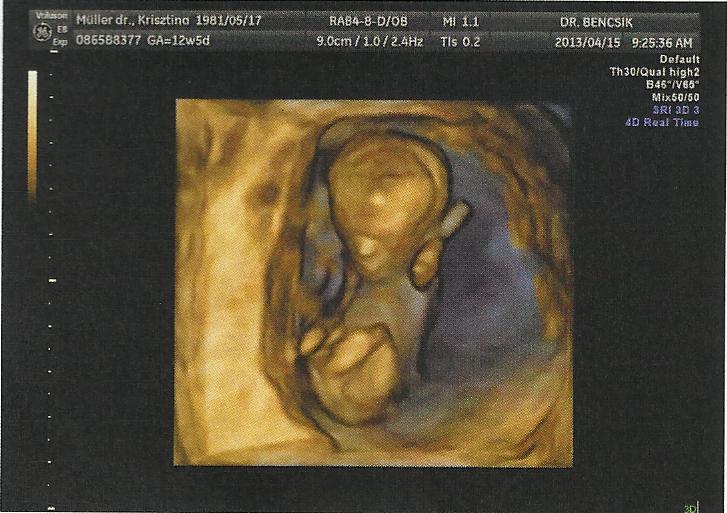

A facebookról értesültünk, hogy a szombathelyi, olimpiai bronzérmes birkózó Hatos Gábor, hamarosan apuka lesz. Több sem kellett, gratuláltunk a sportolónak, aki elmondta: várhatóan október 23-án fog megszületni gyermeke.

Bár a fiatal pár egyelőre még az elején van a terhességnek, azért megkérdeztük, kislányt vagy kisfiút várnak – e?

- Az orvos azt mondja, fiú, de ki tudja. Ha tényleg kisfiam lesz akkor talán Gábornak fogjuk hívni – mesélte lelkendezve a kispapa.